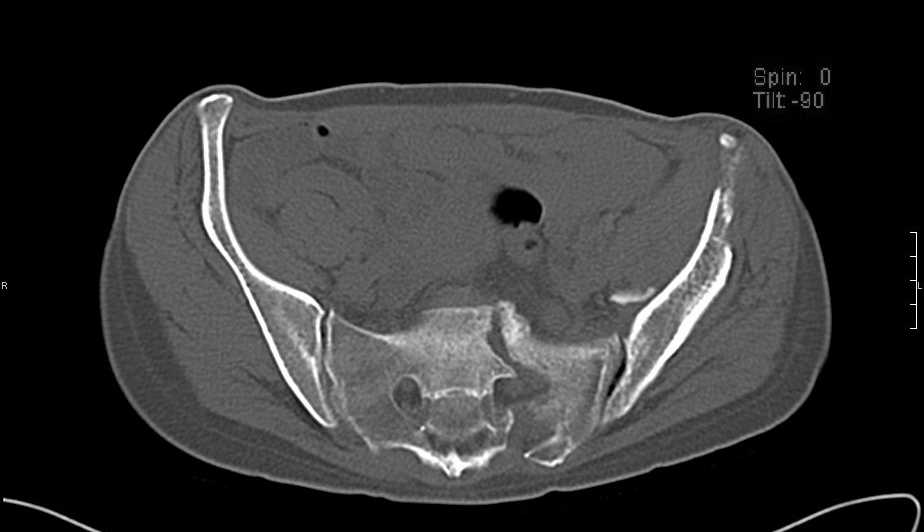

Больная 43 года (промышленный альпинист), 28.07.08 в результате падения с 5 этажа получила политравму: Перелом свода и основания черепа. Вертикально-нестабильное повреждение таза, осложнённое разрывом мочевого пузыря. Чрезвертельный перелом левого бедра. Перелом правой таранной кости, переломовывих правой кубовидной кости. Тупая травма живота, разрыв печени, ушиб почек. Забрюшинная гематома. В день травмы - лапаротомия, ушивание ран печени. Разрыв мочевого пузыря не диагностирован. Течение болезни осложнилось развитием мочевого затёка и обширной пред- и забрюшинной флегмоны, сформировался свищ мочевого пузыря. 19.8.2008 вскрытие, дренировние флегмоны, ревизия мочевого пузыря, обтурация мочевого свища (свищ закрылся в октябре), 1.10.2008 некрэктомия, пластика по Шеде-Лидскому правой кубовидной кости. По результатам КТ диагностирован рак правой почки (диагностическая находка), 8.10.2008 нефрэктомия справа. Переломы велись консервативно. Имеется вертикальное смещение левой половины таза с выраженным отведением крыла (клинически подвижности нет), несросшийся низкий двухколонный перелом левой вертлужной впадины с потерей конгруэнтности, укорочение около5 см, застарелый разрыв лонного сочленения, неправильно сросшиеся переломы обеих ветвей правой лонной кости с укорочением, патологическая подвижность лоно-седалищного фрагмента слева. Правая нижняя конечность неопорна, несмотря на то, что лежа прямую ногу поднимает, ходит на левой ноге (ортопедическая обувь) с костылями, справа тазобедренный ортез. Седалищные нервы работают.Урологи отпустили больную на 6 мес.

с большей вероятностью пациентка придет к эндопротезированию тазобедренного сустава, поэтому необходимо создать надежную "опору" сзади и подготовить бедро к имплантации любой классической ножки.ИМО бедренной кости GN, АНФ на таз,по необходимости остеотомия крестца, восстановление конфигурации задних отделов и устранение вертикального смещения половины таза. дождаться сращения крестца и бедренной кости. второй этап эндопротезирование: ножка цвай-мюллер или спаторно,ацетабулярно онкологическое антипротрузионное кольцо левое либо ацетабулярный компонент по индивидуальным параметрам для протезирования после резекции лонной седалищной костей и вертлужной впадины при онкопатологии. в кольцо пару трения металл\металл с цементной чашкой IMPLANTCAST, т.к. пациентка молодая.лонные кости можно оставить в покое, какой никакой рубец есть. с уважением Сергей.